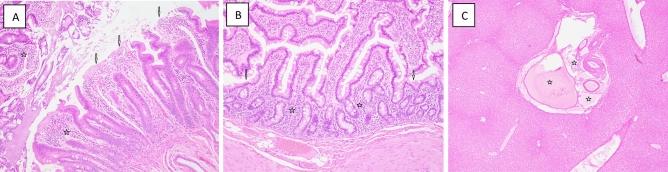

Exposure to high, marginally lethal doses or higher of ionizing radiation, either intentional or accidental, results in injury to various organs. Currently, there is only a limited number of safe and effective radiation countermeasures approved by US Food and Drug Administration for such injuries. These approved agents are effective for only the hematopoietic component of the acute radiation syndrome and must be administered only after the exposure event: currently, there is no FDA-approved agent that can be used prophylactically. The nutraceutical, gamma-tocotrienol (GT3) has been found to be a promising radioprotector of such exposure-related injuries, especially those of a hematopoietic nature, when tested in either rodents or nonhuman primates. We investigated the nature of injuries and the possible protective effects of GT3 within select organ systems/tissues caused by both non-lethal level (4.0 Gy), as well as potentially lethal level (5.8 Gy) of ionizing radiation, delivered as total-body or partial-body exposure. Results indicated that the most severe, dose-dependent injuries occurred within those organ systems with strong self-renewing capacities (e.g., the lymphohematopoietic and gastrointestinal systems), while in other tissues (e.g., liver, kidney, lung) endowed with less self-renewal, the pathologies noted tended to be less pronounced and less dependent on the level of exposure dose or on the applied exposure regimen. The prophylactic use of the test nutraceutical, GT3, appeared to limit the extent of irradiation-associated pathology within blood forming tissues and, to some extent, within the small intestine of the gastrointestinal tract. No distinct, global pattern of bodily protection was noted with the agent's use, although a hint of a possible radioprotective benefit was suggested not only by a lessening of apparent injury within select organ systems, but also by way of noting the lack of early onset of moribundity within select GT3-treated animals.